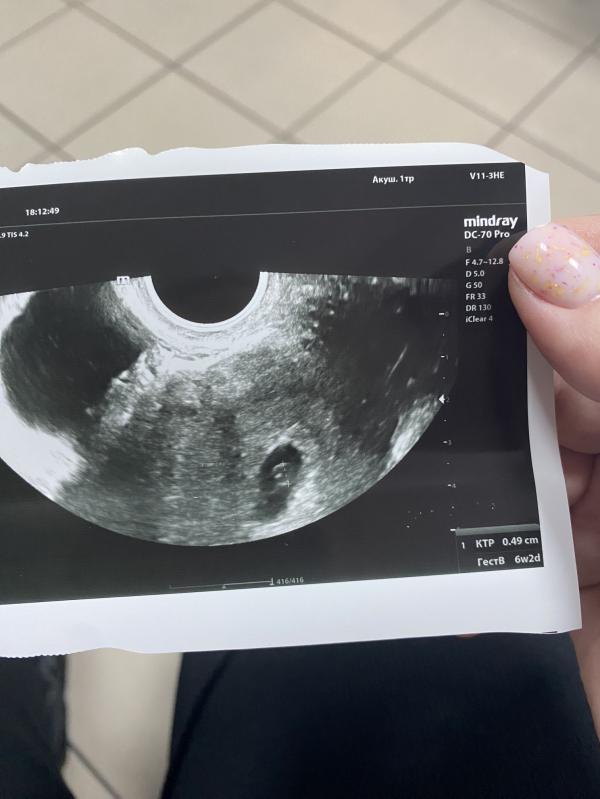

Креветка выросла ❤️❤️❤️

Сердце бьется, дали немного послушать, это такой кайф! Через неделю проверить еще раз, видимо только-только начинает работать, не сразу поймала.

Все соответствует сроку❤️